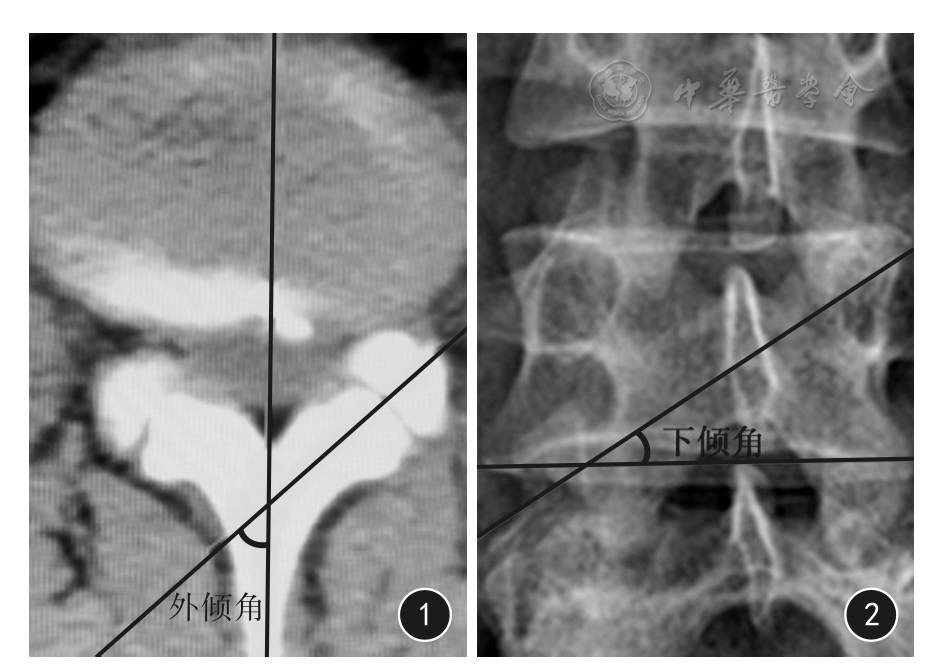

螺钉经过上位椎体进钉侧椎弓根的中心,并指向对侧的关节突关节,此时螺钉尖端进至棘突(图3A)。在侧位X线透视下,进钉位置显示螺钉尖端应在上位椎体棘突与椎板结合点的中下1/3处并距离椎板后缘约5 mm,螺钉尖端指向关节突关节(图3B)。在45°斜位X线透视下,进钉位置应在上位椎体棘突根部的中下1/3处,螺钉尖端位于椎板前后缘投照线之间并指向关节突关节中心(图3C)。

3 椎体标本经椎板关节突螺钉进钉点X线片 3A 前后位 3B 侧位 3C 45°左后斜位

4 椎体标本经椎板关节突螺钉进钉过程X线片 4A 前后位 4B 侧位 4C 45°左后斜位

5 椎体标本经椎板关节突螺钉进钉完成X线片 5A 前后位 5B 侧位 5C 45°左后斜位

2.2 进钉过程中的影像学特征

在脊柱前后位X线透视下,螺钉轨迹示螺钉尾端始终经过上位椎体进钉侧椎弓根的中心,螺钉尖端穿过棘突进入对侧椎板,位于棘突与关节突关节之间并始终指向对侧的关节突关节(图4A)。在侧位X线透视下,螺钉轨迹示螺钉尖端已进入上位椎体棘突与椎板结合点的中下1/3,位于椎板前后缘投照线之间并始终指向关节突关节,同时也指向下位椎体椎弓根的后部(图4B)。在45°斜位X线透视下,螺钉尖端已穿过上位椎体棘突根部的中下1/3处,位于椎板前后缘投照线与关节突关节间隙之间,并始终指向关节突关节中心与横突上缘(图4C)。

2.3 进钉完成后的影像学特征

在脊柱前后位X线透视下,螺钉轨迹示螺钉尾端抵达进钉点,即上位椎体棘突的中下1/3处,钉尾延长线经过上位椎体进钉侧椎弓根的中心,螺钉尖端穿过对侧的关节突关节,抵达下位椎体椎弓根外上缘与横突上缘之间(图5A)。在侧位X线透视下,螺钉尾端抵达进钉点,即上位椎体棘突与椎板结合点的中下1/3并稍向后约5 mm处,螺钉尖端穿过关节突关节,接近椎弓根,终止于椎弓根的后上缘(图5B)。在45°斜位X线透视下,螺钉尾端抵达进钉点,即上位椎体棘突根部的中下1/3处,螺钉尖端穿过关节突关节,到达上关节突的前缘(图5C)。